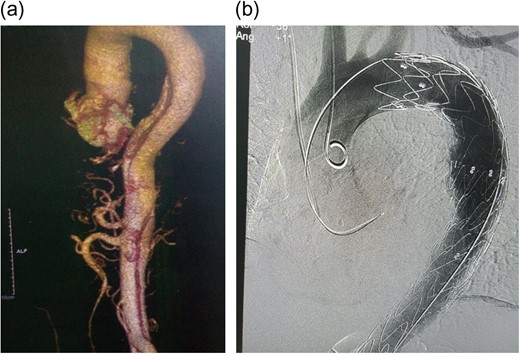

On examination, he had a blood pressure of 172/119 (right arm) and 137/92 (left arm). The rest of the cardiac examination was unremarkable. He had a full complement of pulses with no bruits or murmurs. High-sensitivity Troponin T was elevated (19.29 ng/ml), but not rising. An electrocardiogram (ECG) and a transthoracic 2D-echocardiogram showed left ventricular hypertrophy and no wall motion abnormalities. A computed tomography aortogram (CTA) was done showing an aortic dissection involving the descending aorta extending to the left common iliac, with iliac, superior mesenteric and both renal arteries arising from true lumen (Fig. 1a). He was admitted to the intensive care unit and started on morphine and labetalol infusion at 2 mg/h.

(a) CT Aortogram showing the dissection, 3D reconstruction; (b) immediate post-TEVAR showing contrast only in true lumen.